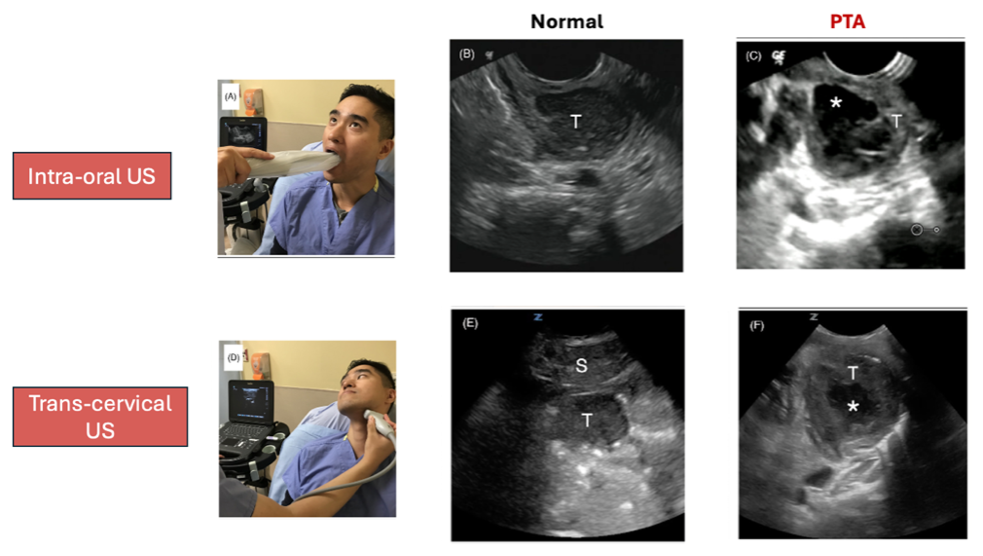

To increase our confidence in diagnosing PTAs in the ED, consider using ultrasound as your 1st line diagnostic modality.

There are 2 main US approaches:

- Intra-oral approach using the endocavitary probe

- Sensitivity: 90-100%

- Remember to topicalize the posterior oropharynx prior to US

- Advantages:

- Better orientation and landmarking for needle aspiration/I&D

- Allow for measurement of depth of internal carotid

- Cons: Limited by patient comfort and level of trismus

- Transcutaneous/transcervical approach using the linear probe

Image source: https://caep.ca/wp-content/uploads/2025/04/Academic-Emergency-Medicine-2023-Kim-Test-characteristics-of-ultrasound-for-the-diagnosis-of-peritonsillar-abscess-A.pdf